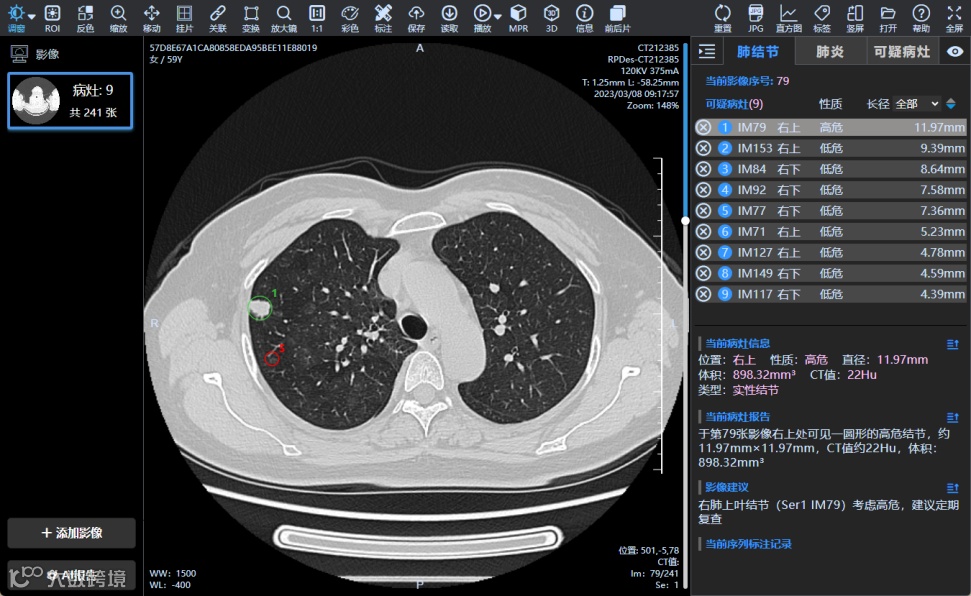

CT智能预测

敏感性高:有效识别微小结节,肺癌早发现早治疗,防止漏诊

特异性高:研发混合注意力机制,提高肺部疾病检出特异度

大规模筛查:独家技术实现阴阳性筛查,有效防控

结构化报告:自动生成结构化报告,提高医生工作效率